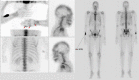

Multifocal chondrosarcoma of the hand: Case report and review of the literature

Few multifocal hand chondrosarcomas have been reported. To our knowledge, this report is the first to describe multifocal hand chondrosarcoma in a patient with no evidence of prior enchondroma, Ollier's disease, or Maffucci syndrome.